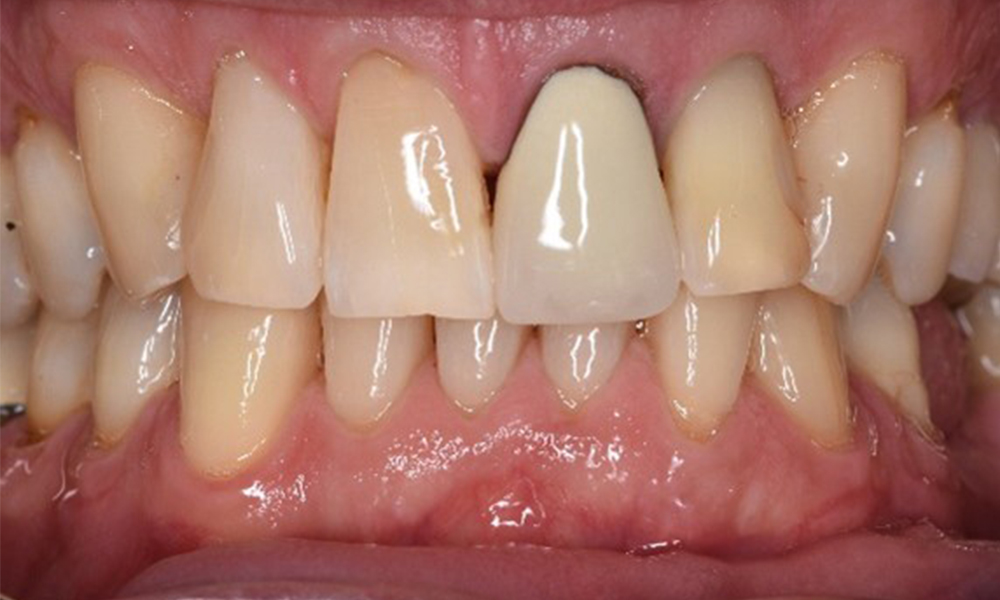

The patient has no particular risk factors with specific dental implications. The key factor, therefore, is the requirement in terms of oral health. In this respect, good oral health is evident with stable, reduced periodontium. Should evidence of an increase in probe depth compared with the baseline, combined with diffuse bleeding, be found at a check-up appointment, diagnosis using X-ray imaging (dental X-ray) should be undertaken in order to identify peri-implant bone loss at an early stage and intervene accordingly.

Despite the stable condition, it is also important for this patient to be given motivation/instruction. Particular attention should be paid to correct care for implants. Here in particular, good at-home maintenance can have a significant impact on the long-term stability of oral and implant health.